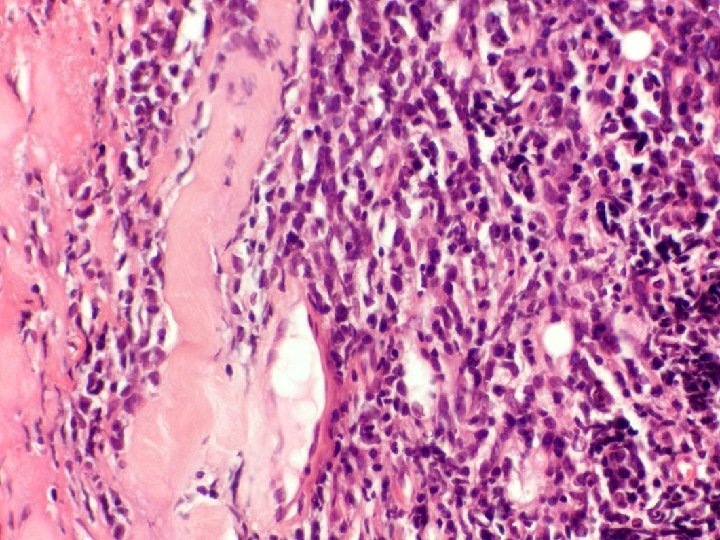

�Case number: 185 �Clinical: Male aged 70 years. ? BCC �Immuno: Pancytokeratin shows strong

�Case number: 185 �Clinical: Male aged 70 years. ? BCC �Immuno: Pancytokeratin shows strong positivity in centre of lymphoid islands. EBV negative.

Most popular diagnosis � Lymphoepithelioma-like carcinoma